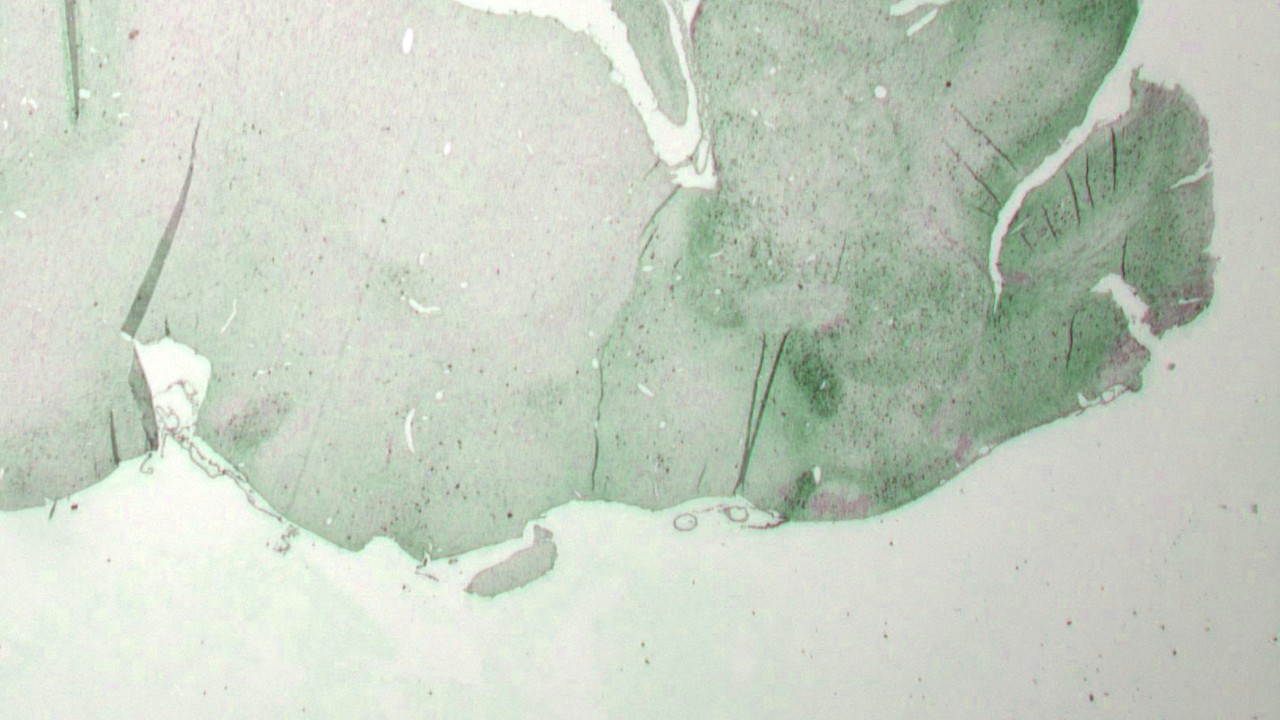

Lundbeck è tenuta per legge a condurre sperimentazione animale per sviluppare farmaci sicuri ed efficaci per la cura dei disturbi psichiatrici e neurologici. Ricorriamo agli esperimenti su animali solo in mancanza di alternative e quando i benefici superano i rischi di nuocere agli animali. I nostri animali ricevono cure adeguate e noi lavoriamo costantemente per migliorare la nostra politica e le procedure di sperimentazione animale, nonché le strutture in cui ospitiamo questi animali.